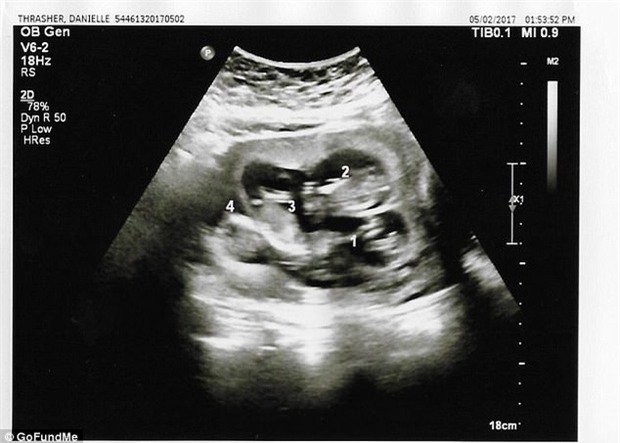

Phải tới lần siêu âm thứ 3 thì các bác sĩ mới phát hiện ra em bé thứ tư nằm trong bụng bà mẹ.

Phải tới lần siêu âm thứ 3 thì các bác sĩ mới phát hiện ra em bé thứ tư nằm trong bụng Danielle.

Tuy nhiên có một điều cả hai vô cùng thắc mắc đó là tại sao đến tận lần siêu âm thứ 3 các bác sĩ mới phát hiện ra em bé thứ tư trong bụng Danielle.

Trả lời về vấn đề này, các bác sĩ làm việc trực tiếp với Danielle giải thích: "Bào thai thứ tư bị che khuất bởi lỗ rốn của Danielle, điều đó khiến chúng tôi không thể nhìn thấy trong những lần siêu âm trước. Còn việc mọi người hỏi rằng tại sao không kiểm tra kĩ trong quá trình siêu âm thì chúng tôi cho rằng việc thai phụ có 3, 4 hay 5 con không nằm trong dự đoán của chúng tôi và chúng tôi không có bất cứ lý do nào để kiểm tra xem liệu thai phụ đang mang bao nhiêu thai, nhất lại là trong những trường hợp như thế này, vị trí nằm của đứa trẻ không khiến chúng tôi đặt bất cứ nghi vấn nào".

Nói thêm về trường hợp của chị Danielle, các bác sĩ cho biết, 4 bào thai trong bụng được tạo thành từ 4 trứng và 4 tinh trùng riêng biệt. Đây là một điều khá hiếm khi xảy ra. Trong 700.000 ca mang thai tự nhiên thì chỉ có 1 ca tương tự như vậy.